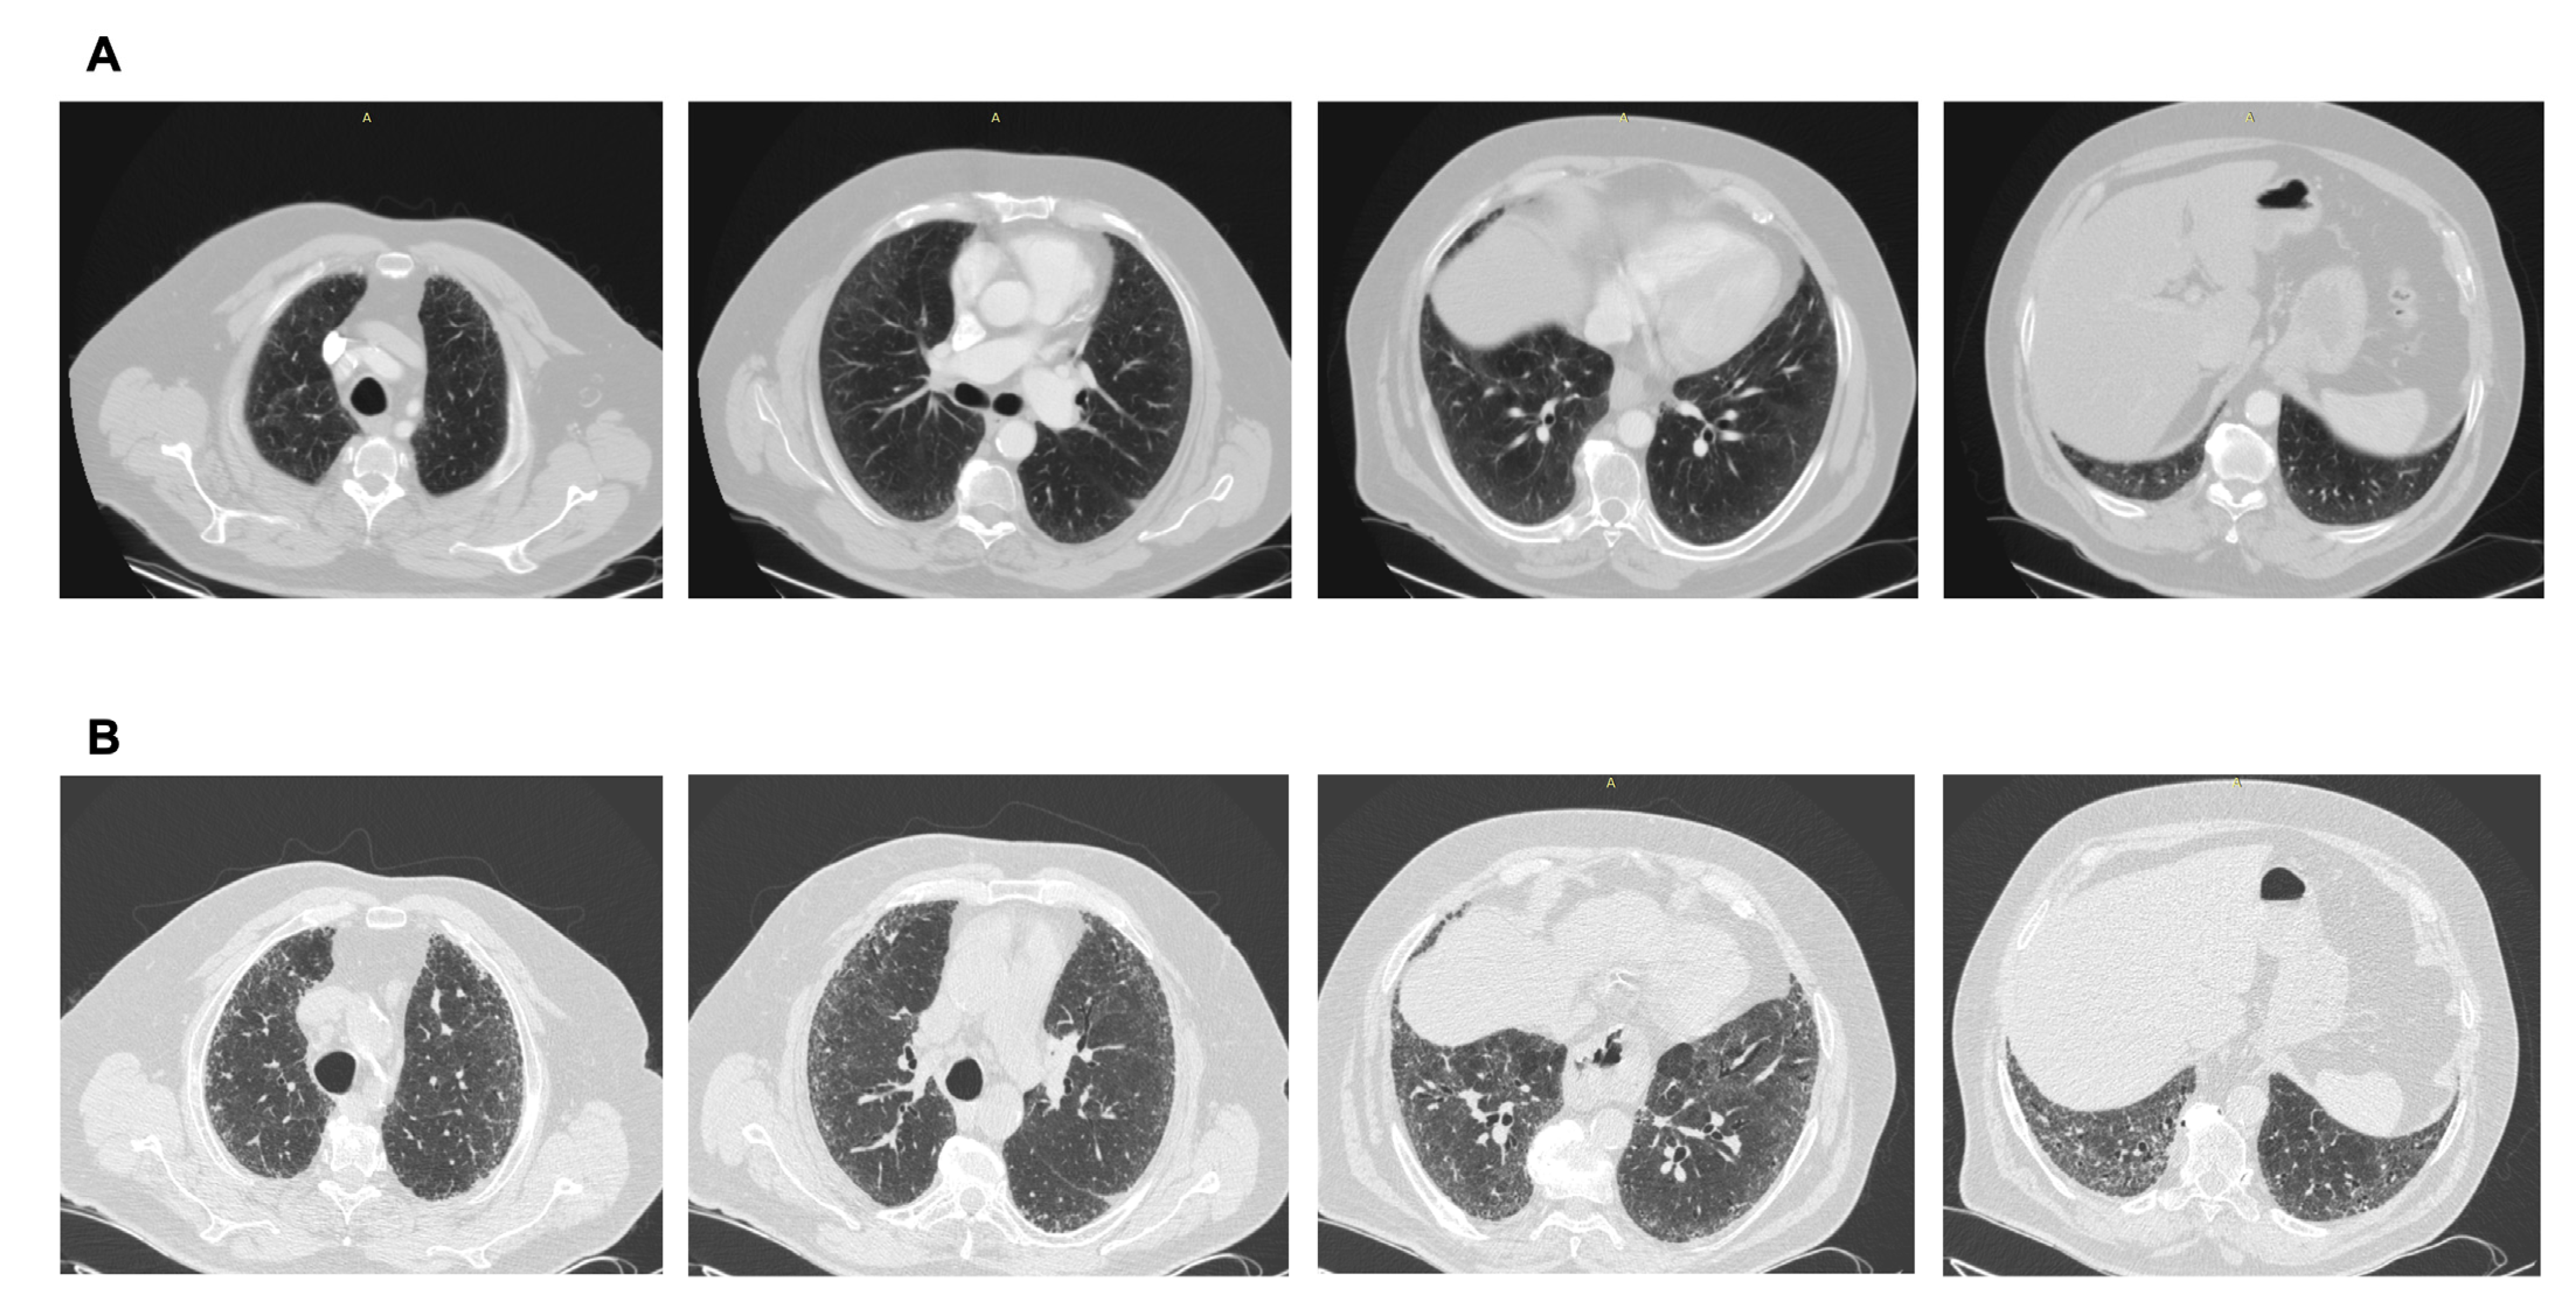

ILAs with a non-subpleural distribution are usually non-progressive and do not have survival implications, while subpleural ILAs, in general, are potentially clinically significant. Fibrotic ILAs are clearly associated with higher odds of ILA progression and increased mortality [11] (Figure 1).

Figure 1.

Radiological types of ILAs.